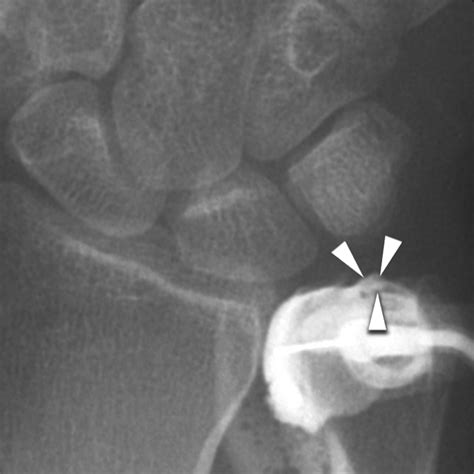

• Imaging Tests: X-rays, MRI, or CT scans may be ordered to visualize the knee joint and confirm the diagnosis. MRI is particularly useful for detecting soft tissue injuries like cartilage tears.